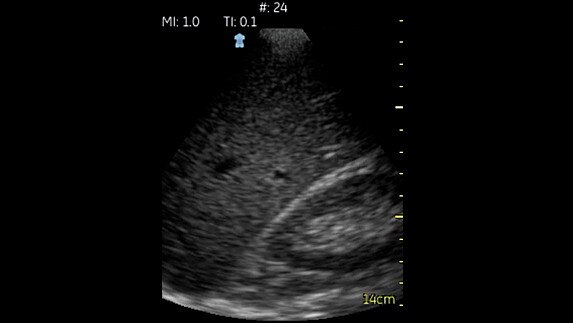

Fazlı abdomen